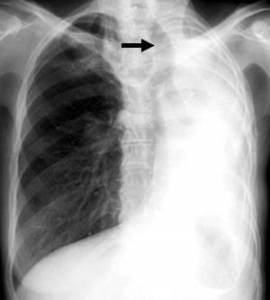

Если кашель не утихает в течение полугода, это может свидетельствовать о наличии туберкулеза. Для выявления причины продолжительных приступов кашля фтизиатр назначает пациенту анализ мокроты и проведение рентгенологических исследований.